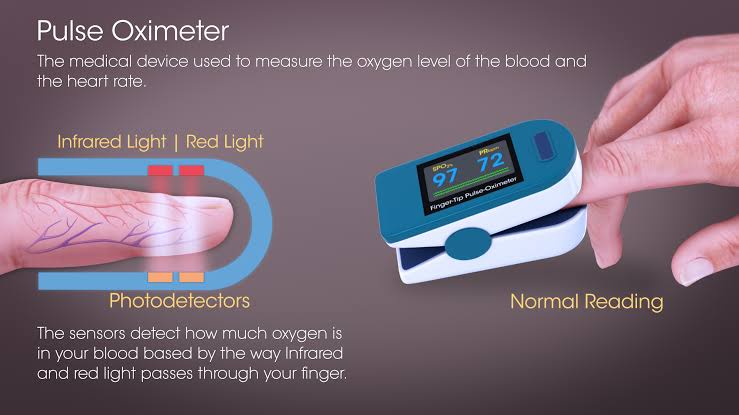

Pulse oximetry (પલ્સ ઓક્સિમેટ્રી):

- પલ્સ ઓક્સિમેટ્રીને ‘ઓક્સિજન સેચ્યુરેશન ટેસ્ટ’ તરીકે પણ ઓળખવામાં આવે છે.

- પલ્સ ઓક્સિમેટ્રી એ ક્વિક, નોન ઇન્વેસીવ ટેકનીક છે જે હિમોગ્લોબીન સાથે જોડાયેલ ઓક્સિજન સેચ્યુરેશનને મોનીટરીંગ કરે છે.

- પલ્સ ઓક્સિમેટ્રીમાં પલ્સ ઓક્સિમીટરનો ઉપયોગ કરવામાં આવે છે. જે એક પ્રકારનું ઇલેક્ટ્રોનિક ડિવાઇસ છે.

- આ ડિવાઇસમાં લાઇટ ઇમિટિંગ ડીઓડ લગાવેલ હોય છે જે સ્પેસિફિક બે જુદી જુદી વેવલેન્થ (ઇન્ફ્રારેડ લાઇટ અને રેડ લાઇટ) ધરાવતી લાઈટને મોટાભાગે ફિંગર ટીપ પર પસાર કરે છે આમાંથી એક લાઈટ એ ઓક્સિજીનેટેડ હિમોગ્લોબીનની સંખ્યા મેઝર કરે છે જ્યારે બીજી લાઇટ ડીઓક્સિજીનેટેડ હિમોગ્લોબીનની સંખ્યા મેઝર કરે છે અને છેવટે ઓક્સિજીનેટેડ હિમોગ્લોબીનની સંખ્યા દર્શાવે છે.

- પલ્સ ઓક્સિમીટરને ફિંગર, ટોસ, ફૂટ, ઇયર અને નોઝમાં પ્લેસ કરવામાં આવે છે અને spo2 લેવલ ચેક કરવામાં આવે છે.

- નોર્મલ spo2 લેવલ 95-100% ની વચ્ચે હોય છે. જો spo2 લેવલ 85% કરતા ઓછું જોવા મળે તો તે દર્શાવે છે કે સેલ અને ટિસ્યુ સુધી પૂરતા પ્રમણમાં ઓક્સિજન પહોચતું નથી.